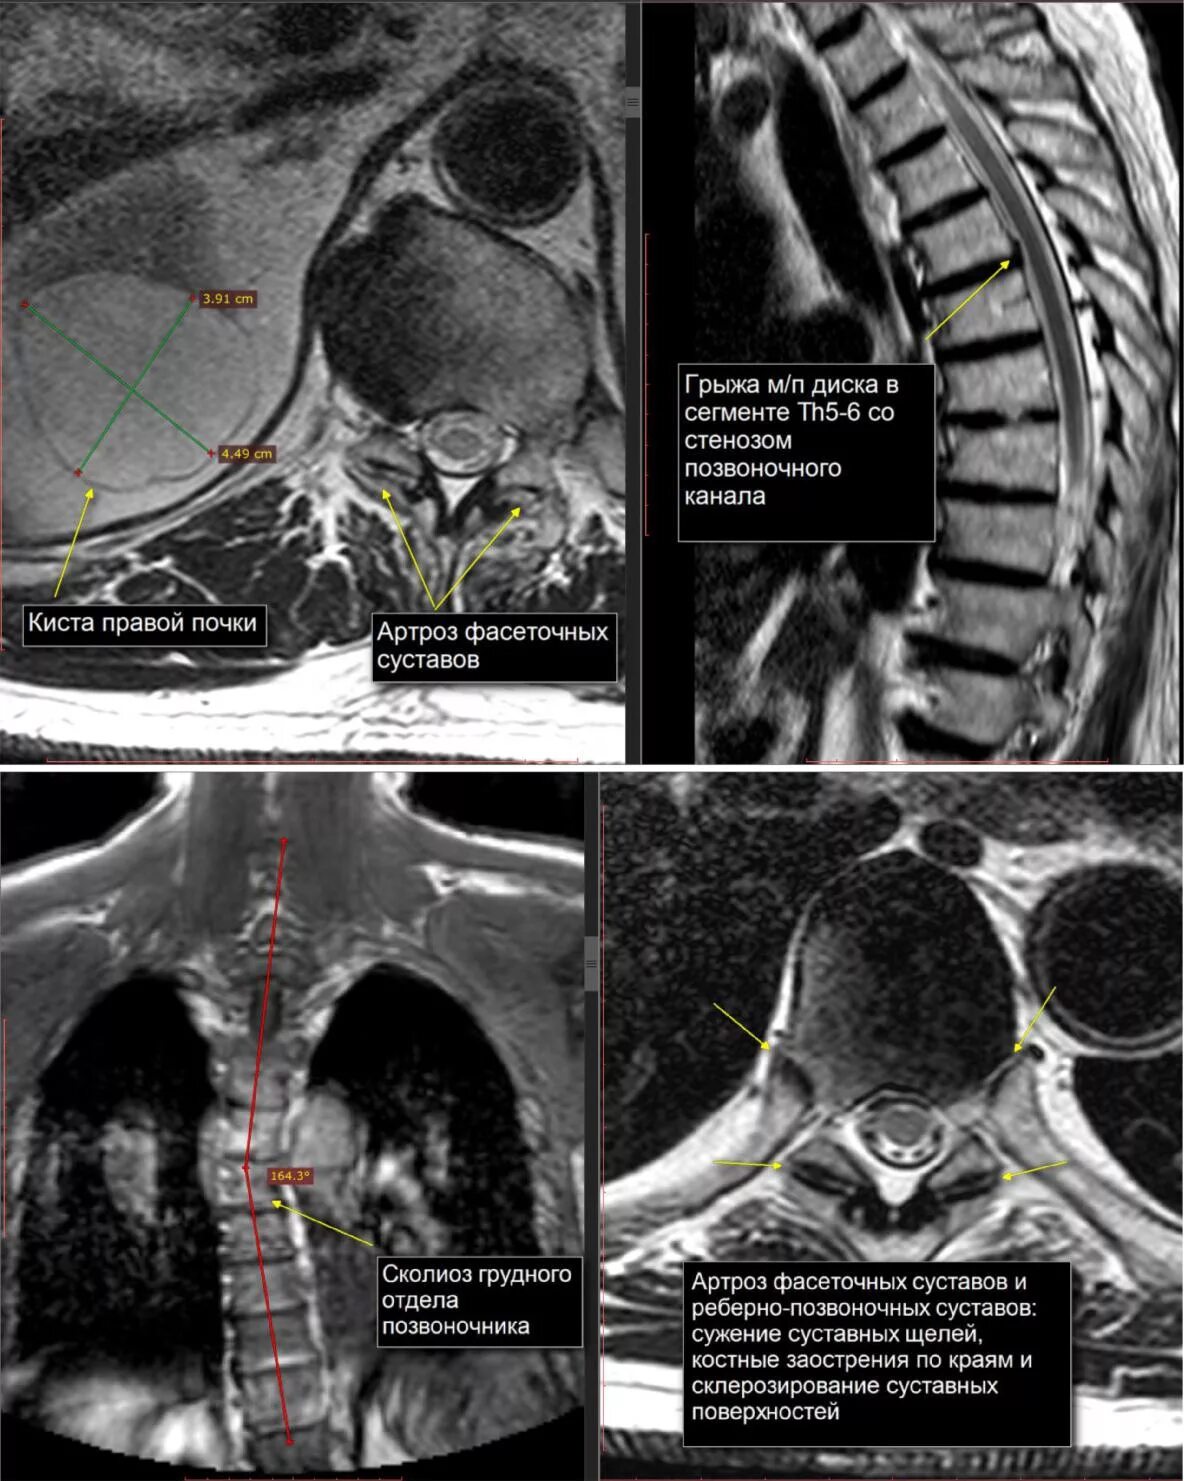

Мр картина дегенеративных